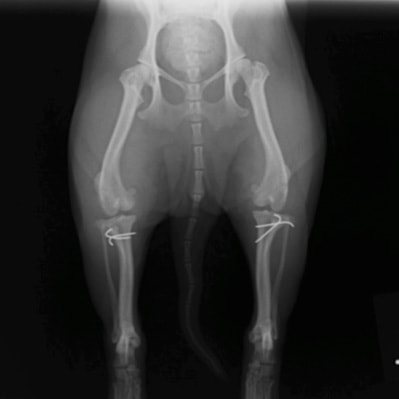

■ 症例20 ポメラニアン 8ヶ月 1.8kg

左右膝蓋骨脱臼 グレードⅢ

2ヶ月前から間欠的跛行が認められ、両膝の膝蓋骨脱臼整復術を行った。

手技は縫工筋及び内側広筋の解放、脛骨粗面の外側転位、滑車ブロック形造溝術、内外側関節包の縫縮を選択し実施した。

右側の膝蓋骨脱臼は上記手技で整復されたものの、左側はそれのみでは膝蓋骨が浮く様子が認められた。その為、PDS縫合糸にて膝蓋靱帯を1糸のみ縫合し、靱帯の縫縮を行った。

膝蓋骨脱臼は膝関節における膝蓋骨の内外側の脱臼と定義されるが、時として単純な内外の脱臼ではなく、膝蓋骨が大きく前方に浮き上がるように脱臼する場合がある。特にトイプードルやポメラニアンといった犬種に多く認められる。

内側脱臼に加えて前方への浮き上がりを矯正する為に、従来より脛骨粗面転移により膝蓋靭帯を外方と下方に引っ張り、固定する方法を選択する。膝蓋骨の前方への浮き上がりが軽度の場合は、従来法ではなく関節包の縫縮で対応していた。しかし、一部の症例で膝蓋骨の動きが悪くなり伸展機構が円滑に機能せずロボット様歩行になるケースがあった。

その為、膝蓋靭帯自体を縫縮する方法を採用した。この方法により、膝関節の伸展機構を妨げず膝蓋骨の軽度の浮きを矯正することが可能となった。

本症例の経過は良好である